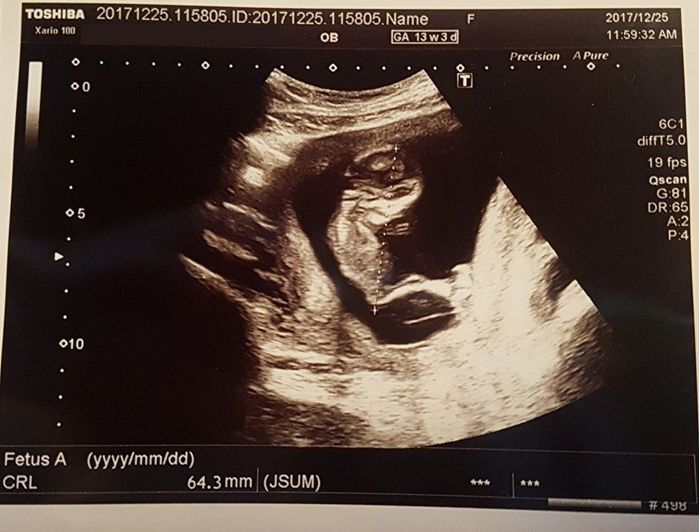

妊娠13週目 不規則抗体!? まさかの診断に動揺

上から頭、体があり、背中とおなかが区別できます。子どもと私がしっかりとつながっていることも、はっきりとわかります。頭の右下に小さな手が見え、指しゃぶりをしているみたい。

血液検査の結果、不規則抗体の疑いがあると診断されました。経過観察をし、結果次第ではNICUのある病院で出産したほうがよいとのこと。一瞬動揺しましたが、深く心配しないように努めました。